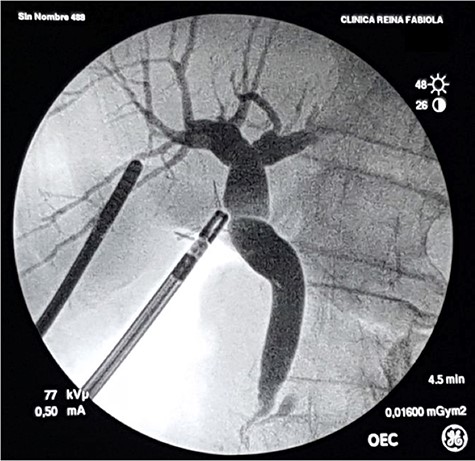

With the patient in supine position, the trocars were placed as per the American technique of LC. After releasing lax adhesions, the remaining cystic duct was recognized and individualized from the CBD with cold scissors. Once isolated, a lateral incision in the cystic stump was made for CBD exploration (Fig. 3). Under radiological guidance, the clip was successfully removed through the cystic duct with endoscopic hose-type biopsy forceps (Fig. 4). A control cholangiography confirmed CBD clearance (Fig. 5). At the end of the procedure, the metallic clip was removed from the abdominal cavity (Fig. 6), and the remnant cystic stump was secured with a PDS Endoloop Ligature in order to avoid any future migration (Video 1 shows our technique). The patient recovered uneventfully and was discharged 3 days after surgery.

Laparoscopic transcystic extraction under intraoperative radiological guidance. Without any contrast injection to facilitate titanium visualization, the metallic clip (red arrow) is recognized in the distal CBD (A), caught with the endoscopic forceps (B) and finally removed from the CBD through the cystic duct (C).